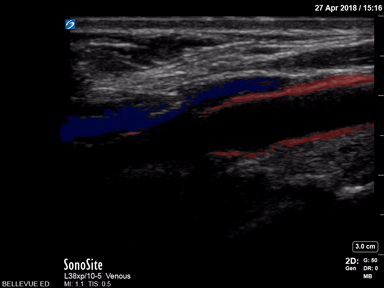

Vascular - Carotid Bulb Long Axis - Colorized

Carotid Bulb (long axis) Red: Common carotid artery, Blue: Lumen of internal jugular vein Images: Dr. Lindsay Davis, Dr. Hannah Kopinski. Image Editing: Michael Amador and Dr. Matthew Riscinti